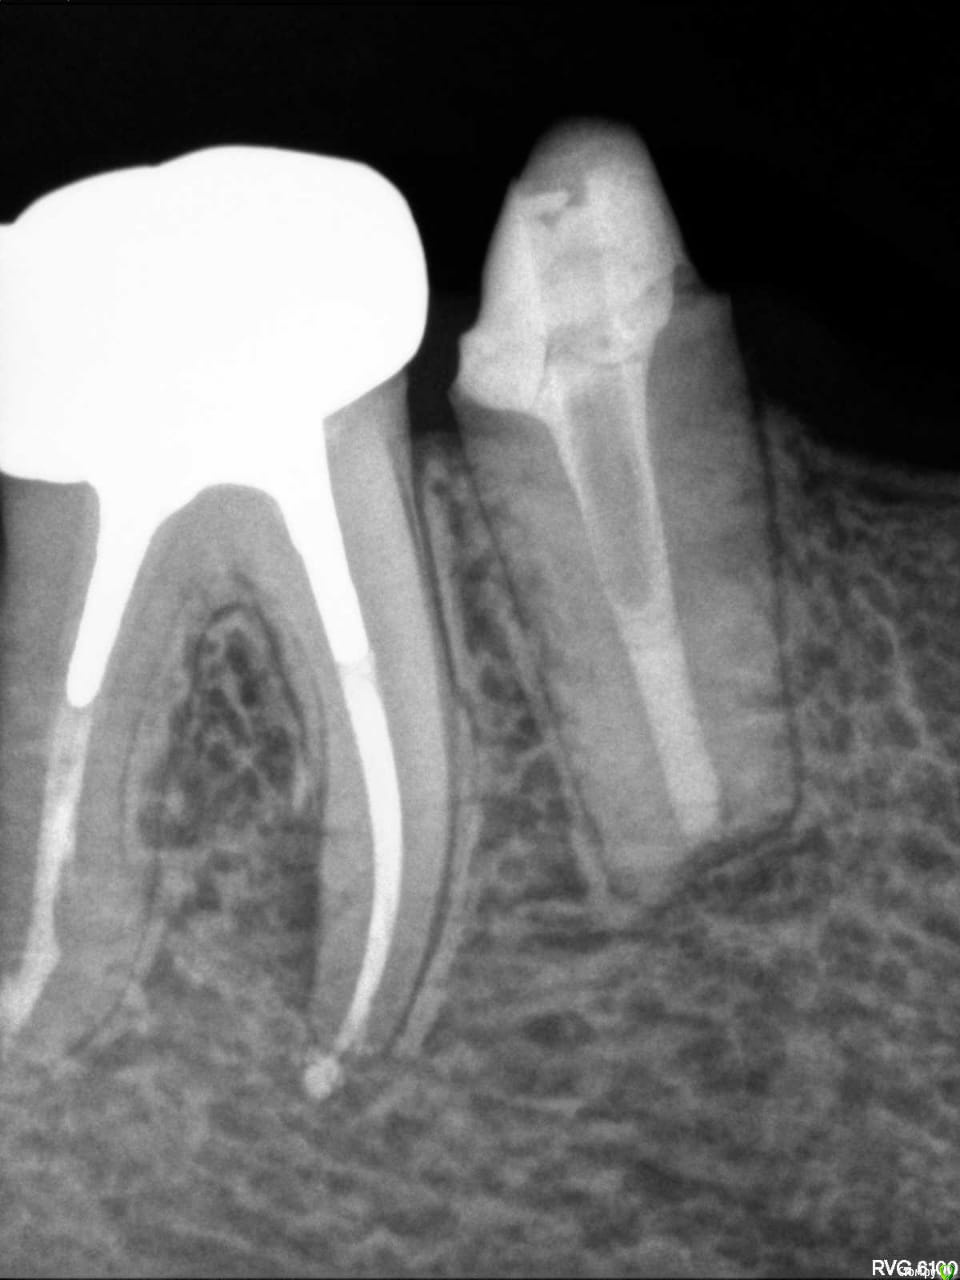

Placeforastep Опубликовано 7 сентября, 2019 Поделиться Опубликовано 7 сентября, 2019 Добрый день, уважаемые стоматологи!Подскажите пожалуйста, этот зуб (6-ка) нужно перелечивать? Если ли на нем киста?Ощущение выросшего зуба и дискомфорт при надкусывании. Ссылка на комментарий

krokomot Опубликовано 7 сентября, 2019 Поделиться Опубликовано 7 сентября, 2019 не весь 6й зуб попал в область прицельного снимка, есть подозрение на наличие воспалительного процесса на боковой стенке корня, там возможно есть ответвление корневого канала. нужно сделать томограмму в эндорежиме и посмотреть зуб в различных срезах и ракурсах. То есть томограмму с высоким разрешением участка с этим зубом. Ссылка на комментарий

Гарриевич Опубликовано 16 сентября, 2019 Поделиться Опубликовано 16 сентября, 2019 по снимку диагноз киста не ставитсяпо вашим жалобам может быть периодонтитгде и как лечили? Ссылка на комментарий